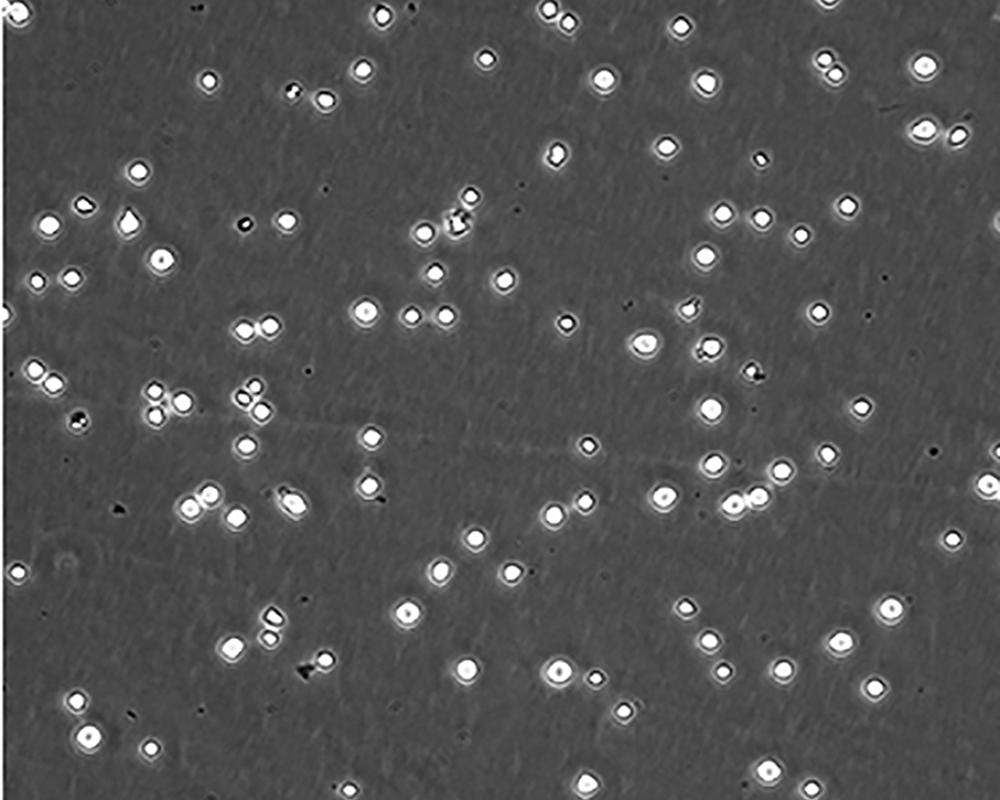

生長特性 suspension

形態(tài)特征 lymphoblast

細(xì)胞描述 CEM/C1是人T細(xì)胞白血病細(xì)胞株CCRF-CEM(見ATCC CCL-119)具有喜樹堿抗性的衍生株。1991年細(xì)胞株選擇并亞克隆了對CPT的抗性。細(xì)胞表現(xiàn)出對CPT類似物水溶性的托泊替康和非水溶性的9-氨基-CPT及10,11-亞甲二氧基-CPT具有交叉抗性。CEM/C1細(xì)胞對CPT的敏感性較母系CEM細(xì)胞低31倍。CEM/C1細(xì)胞表現(xiàn)非典型的多藥抗性和轉(zhuǎn)換拓補(bǔ)異構(gòu)酶I催化活性。對CPT的抗性維持6個(gè)月以上。